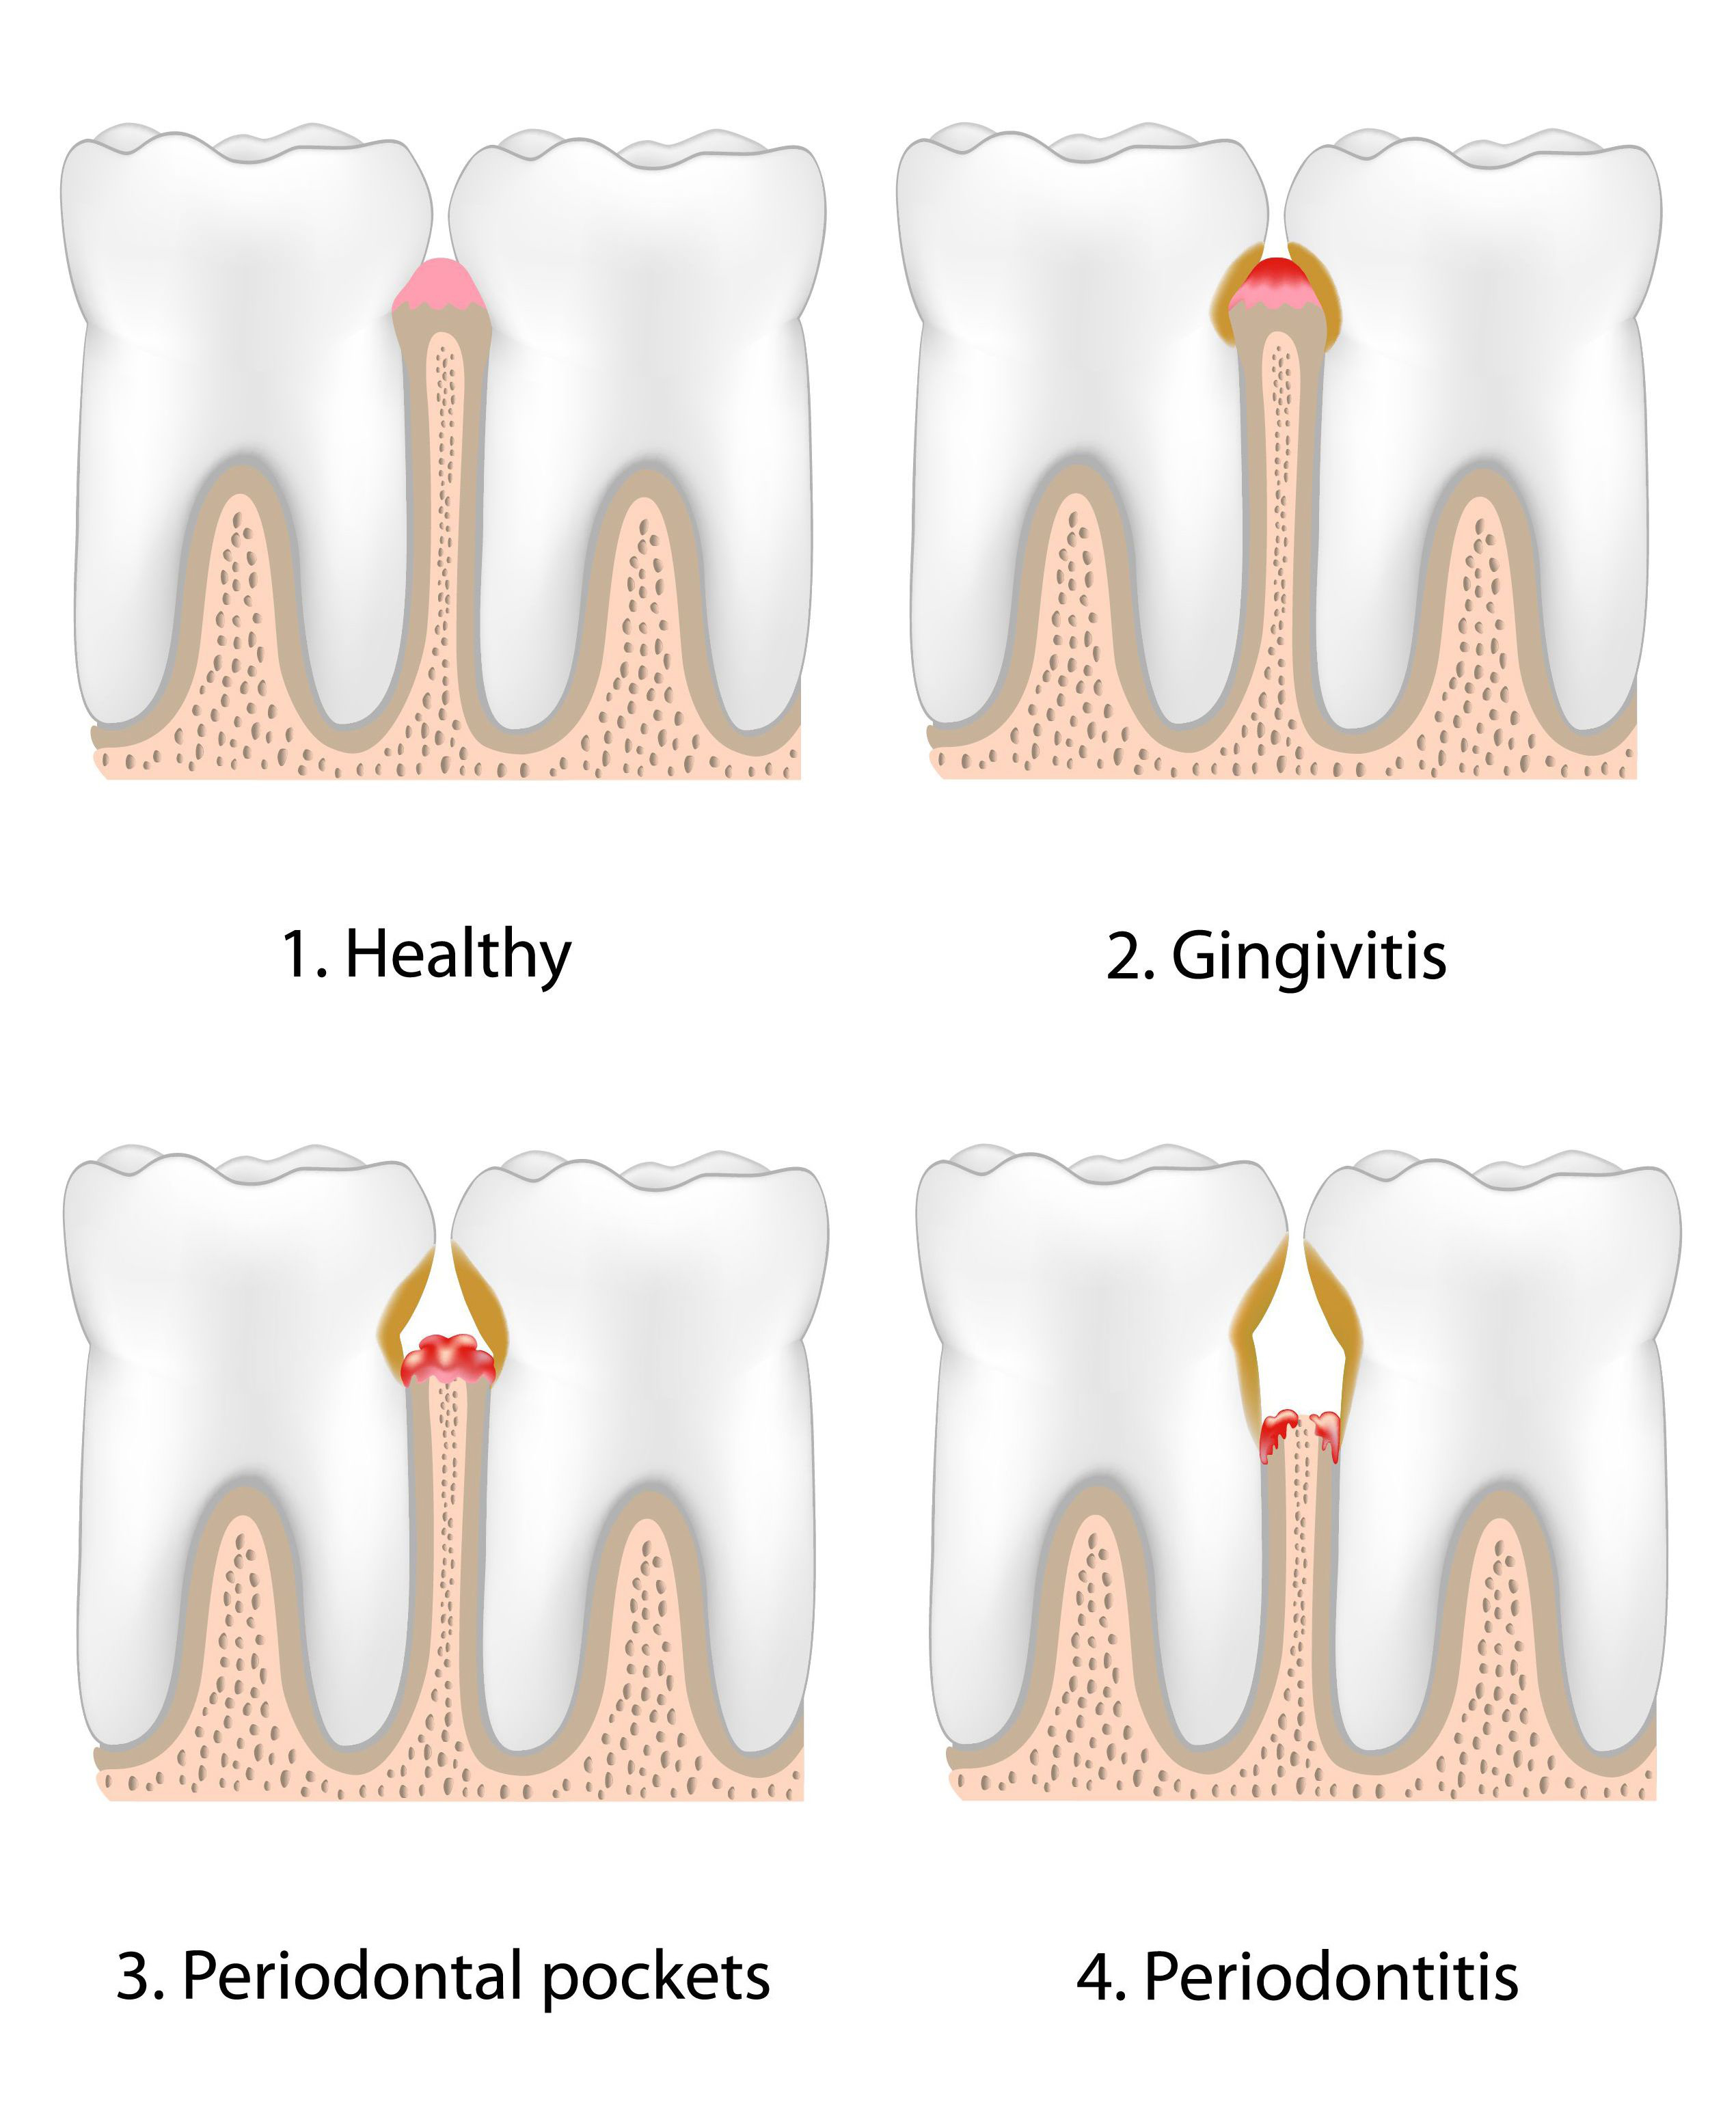

Although serious gum infections aren’t extremely common, they can lead to major issues if not treated in a timely manner. While most of us want to keep our teeth and gums healthy, your gums can be prone to gum infection if not cared for properly. Identifying warning signs that can lead to infected gums is an important way to help prevent further gum disease and all the side effects that come with it.